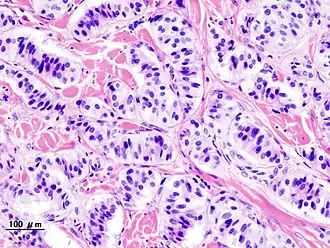

Exame histopatológico de um tumor endócrino pancreático (insulinoma).